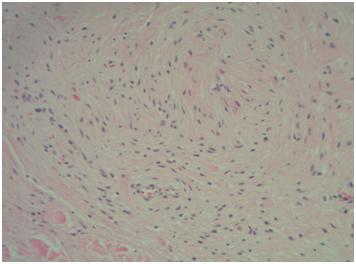

The pathological outcome for both tonsils was lymphoid hyperplasia. Gross examination for the left soft palate mass showed a pink-tan, soft, multilobulated, polypoid portion of smooth, shiny, rubbery tissue that measured 3.0 x 2.7 x 2.0cm. A sectioned portion of the specimen revealed multinodular, tan, rubbery, whorled cut surfaces (Figure 1 & 2). The initial pathologic diagnosis of the left soft palate mass was a benign plexiform lesion, however, the negative staining for S100 (Figure 3) and positive staining for smooth muscle actin (Figure 4) suggested myofibroblastic differentiation. Morphological features of the mass suggested a plexiform neurofibroma. Hence, combining the morphologic appearance with the findings from the Immunostains a new diagnosis favored plexiform leiomyoma.

Figure 1 Soft palate plexiform leiomyoma-Sub mucosal tumor. (Hematoxylin and Eosin stain, Magnification x 100).